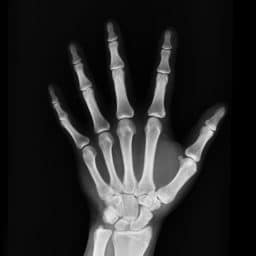

An estimated 54 million Americans have osteoporosis, a condition in which bone mass becomes less dense over time, increasing the risk of suffering a fracture.

Bones most susceptible to fracture are those in the hips, spine and wrist.

Sound waves entering the ear are funneled to the eardrum, a thin membrane attached to the ossicles – a trio of tiny (and extremely fragile) bones in the middle ear.

Because osteoporosis weakens bones, the ossicles are even more vulnerable to fracture in patients with the bone density disease.

Damage to the ossicles results in hearing loss.